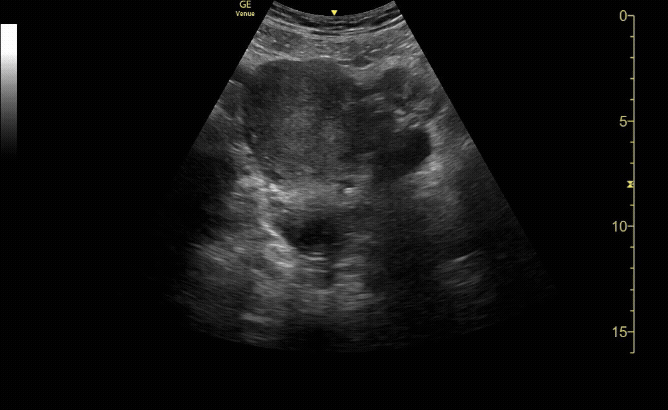

Transverse view of the uterus with no IUP and a left adnexal mass consistent with early ectopic pregnancy

c/o Victoria Gonzalez, MD